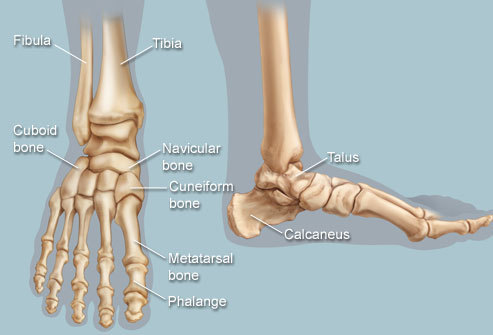

7. 어떠한 뼈들이 후족부(hindfoot), 중족부(midfoot), 전족부(forefoot)를 형성하는가?

•  후족부(Hindfoot)는 종골(calcaneus)과 거골(talus)로 구성된다.

•  중족부(Midfoot)는 주상골(navicular)과 세 개의 설상골(cuneiform bones), 입방골(cuboid)로 구성된다.

•  전족부(Forefoot)는 중족골(metatarsasl)과 지골(phalanges)으로 구성된다.

△ Anatomical illustration of human foot

(이미지 출처 : http://www.webmd.com/pain-management/picture-of-the-feet)